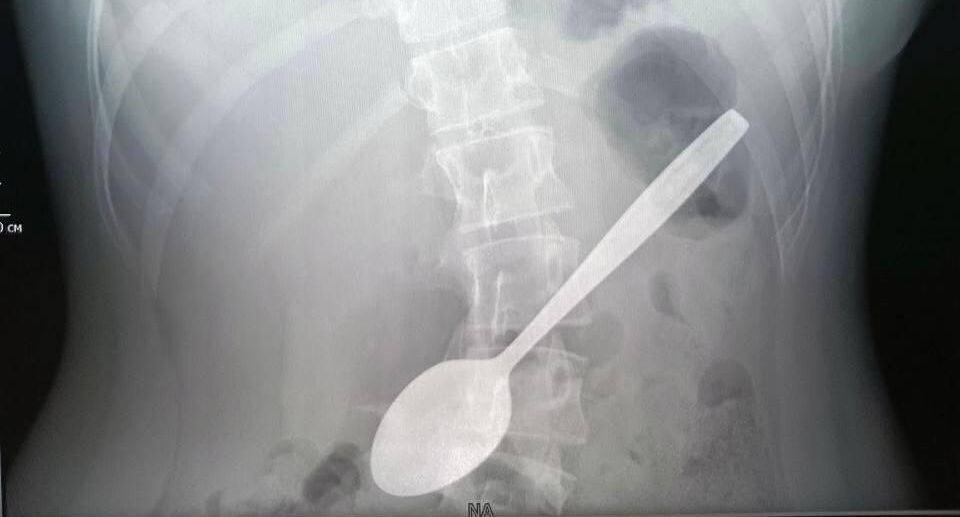

Специалисты Детского клинического центра имени Л. М. Рошаля спасли 14-летнюю пациентку, случайно проглотившую ложку. Школьница с ее помощью пыталась достать из горла застрявший кусок яблока. Врачи сделали девочке рентген органов брюшной полости, который подтвердил, что в желудке находится ложка длиной 15 сантиметров. Ситуация осложнялась тем, что предмет застрял. «Эндоскопической петлей мы извлекли ложку из луковицы двенадцатиперстной кишки, а после эндоскопическими щипцами по типу „крысиный зуб“ протянули ее до глотки. После этого хирургическим зажимом полностью извлекли инородное тело из организма девочки», — пояснила врач Дарья Степаненко. Вмешательство длилось около часа. Сейчас школьница чувствует себя хорошо и находится дома. Специалисты предупреждают, что попавшие в желудок металлические предметы способны привести к пролежням, перфорации стенки или непроходимости, поэтому их необходимо извлечь как можно скорее. Автор: Елизавета Теличенко

Врачи сделали девочке рентген органов брюшной полости, который подтвердил, что в желудке находится ложка длиной 15 сантиметров. Ситуация осложнялась тем, что предмет застрял.